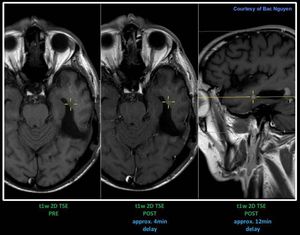

MRI Neuro Imaging – Post GD Take a closer look at the lesion post contrast transversal, approx. 4min delay compared to the post contrast sagittal. Stronger enhancement at the sagittal due to longer waiting time. Just wanted to highlight that waiting time do count, but how long should we wait is another question. #s_mri #siemens #mri #neuro #gadolinium